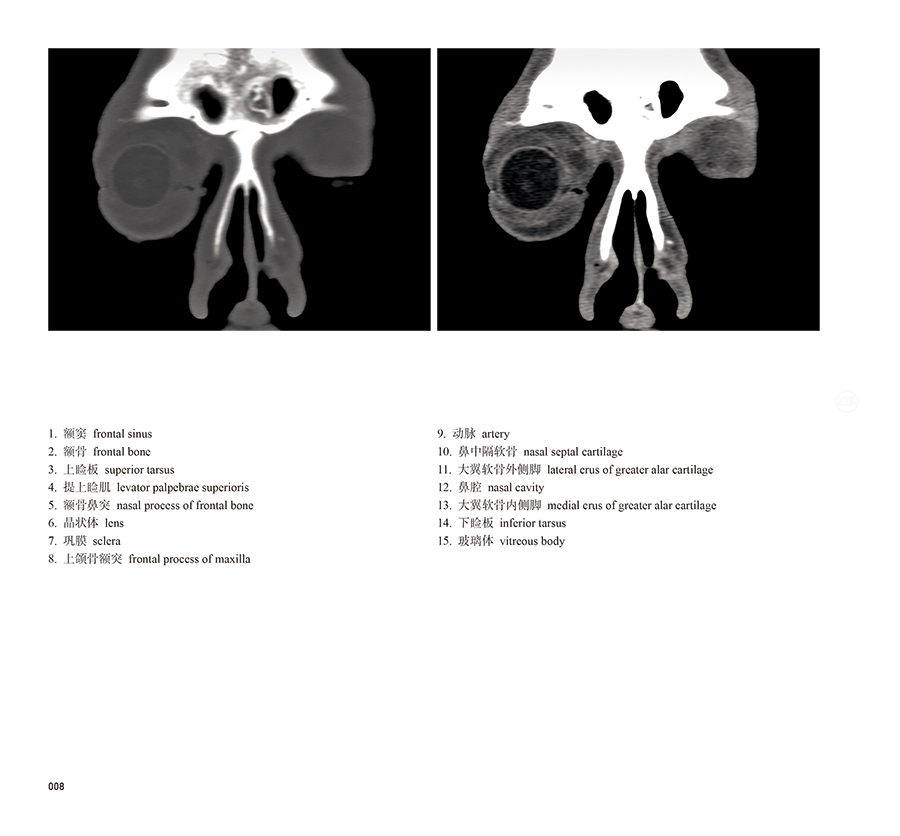

本书从数据集每隔1.2mm选取一幅图像,截取眼、耳、鼻及毗邻颅底的局部区域图像,共112幅图像。同时配以相应部位的CT图像对照。本书特色是断层解剖图利用数字图像处理技术优势,放大并清晰展示眼、耳、鼻及毗邻颅底断面的局部区域结构,组织色泽真实,甚至能够清晰显示肌肉纹理、筋膜纹路等细节结构,图像质量高于美国《人体断层解剖学彩色图谱》(引进版)类似图谱图像质量。对眼科、耳鼻咽喉科和神经内外科医生理解相关解剖结构有较大帮助。